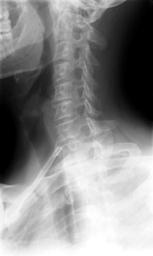

MAKE A MEME View Large Image Cervical Xray Lower Lateral View.jpg en X-ray of cervical spine neck lateral side view This series of x-rays were part of pre-surgical evaluation to help identify spinal instability Patient is a 37 year old male with a history of multiple ...

Keywords: Cervical Xray Lower Lateral View.jpg en X-ray of cervical spine neck lateral side view This series of x-rays were part of pre-surgical evaluation to help identify spinal instability Patient is a 37 year old male with a history of multiple neck traumas with pain and muscle spasms and dental implant in lower jaw Excerpt from radiologist's report FINDINGS Five views of the cervical spine including flexion and extension were performed There is no evidence of fracture bone destruction or malalignment There are degenerative bone and is changes at C5-6 There is no evidence of cervical instability on the flexion and extension views The facet joints are well aligned Bony spurring is narrowing the C5-6 neural foramina bilaterally IMPRESSION Degenerative changes at C5-6 No evidence of instability Ragioagraphie aux raysons X du rachis cervical cou vue latérale côté Cette série de radiographies faisaient partie de l'évaluation pré-chirurgicale pour aider à identifier une instabilité vertébrale Le patient est un homme de 37 ans ayant des antécédents de traumatismes multiples cou avec des spasmes et des douleurs musculaires et implant dentaire à la mâchoire inférieure Extrait du rapport du radiologiste RÉSULTATS Cinq vues de la partie cervicale de la colonne vertébrale ont été faites dont en flexion et en extension Il n'y a pas de signe de fracture de destruction osseuse ni de défaut d'alignement On observe un phénomène de gégénérescence osseuse des changements en C5-6 Il n'existe aucune preuve de l'instabilité du cou sur les radios montrant la flexion et l'extension Les facettes articulaires sont bien alignés Bony spurring is narrowing the C5-6 neural foramina bilaterally IMPRESSION Changements dégénératifs eu C5-6 Aucune preuve d'instabilité own medical image work for hire Stillwaterising 2010-04 File Cervical Xray Extension jpg File Cervical Xray Extension view jpg File Cervical Xray Lateral View jpg Magnification 0 4x converted from lossy DICOM file Cc-zero Oblique X-rays of the neck Human anatomy cervical vertebrae